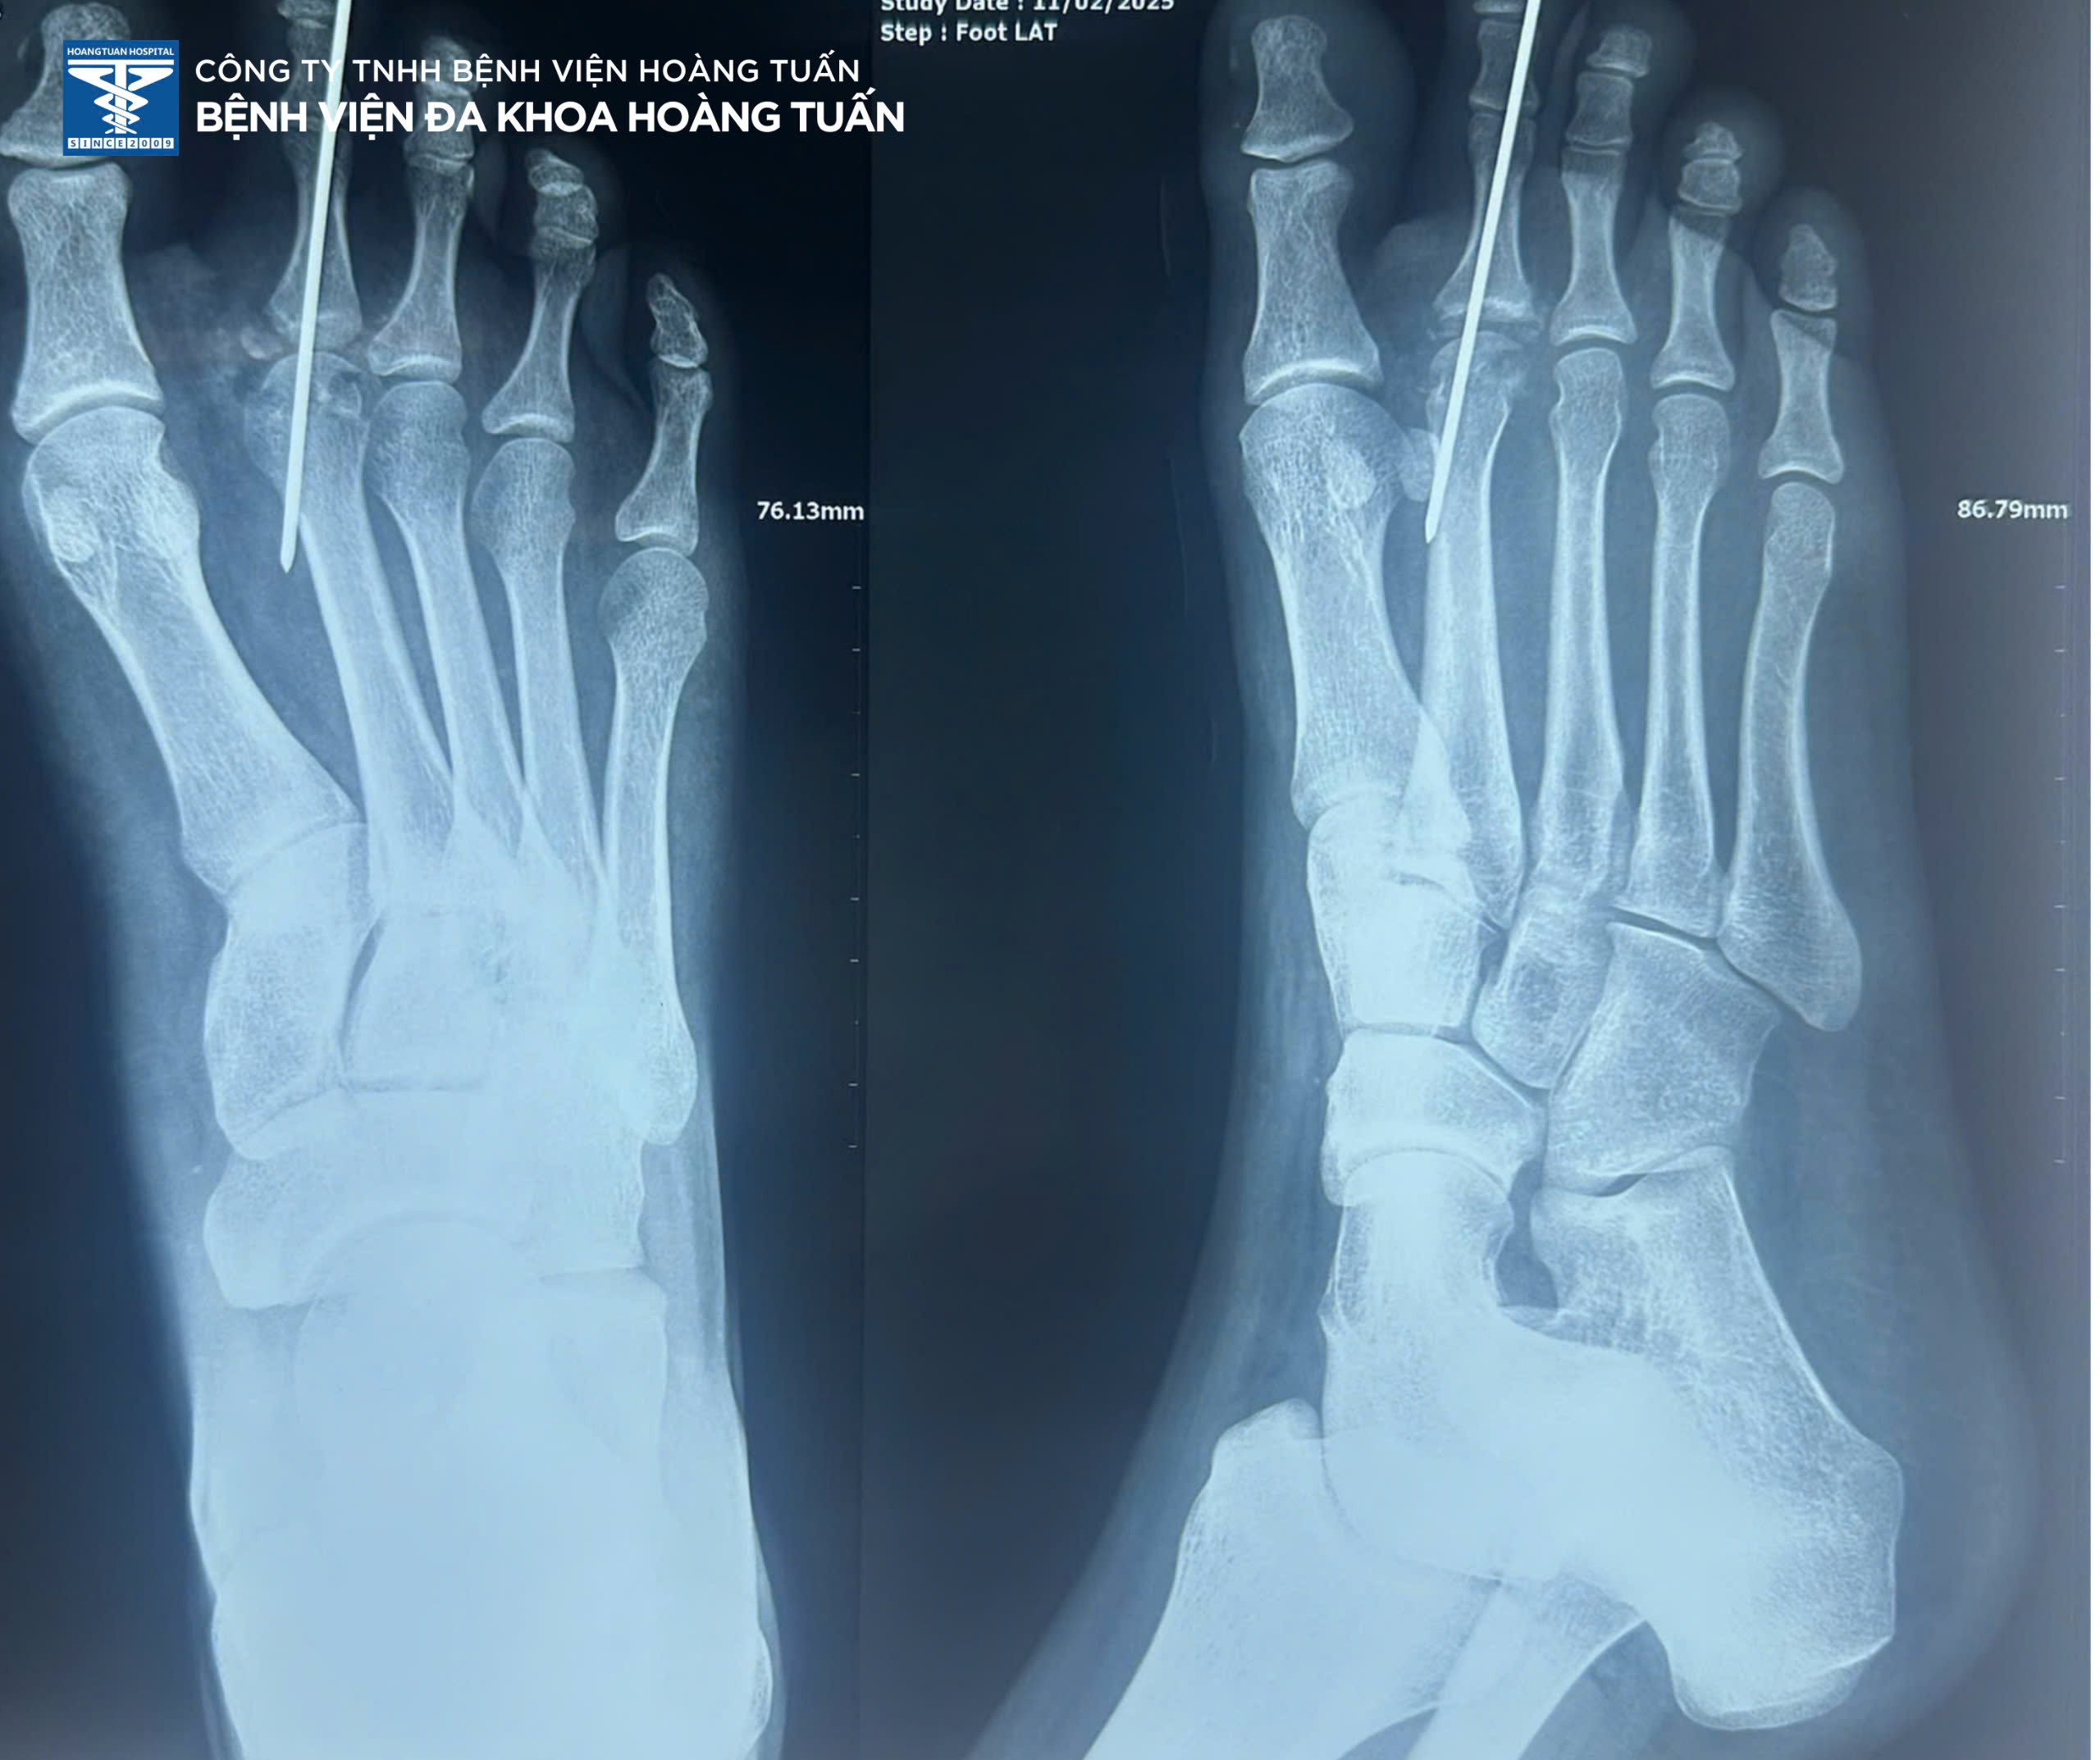

• Vừa qua, Bệnh viện Đa khoa Hoàng Tuấn vừa tiếp nhận một trường hợp bệnh nhân nữ trẻ tuổi vào viện vì đau, chảy máu nhiều vết thương vùng bàn ngón chân phải sau tai nạn giao thông. Qua thăm khám và chụp X-quang vùng bàn ngón chân phải kiểm tra, phát hiện gãy vùng xương bàn ngón II bên phải. Ban lãnh đạo Bệnh viện và Bác sĩ Ngoại Chấn thương hội chẩn và thống nhất quyết định phẫu thuật điều trị phục hồi vùng xương gãy.